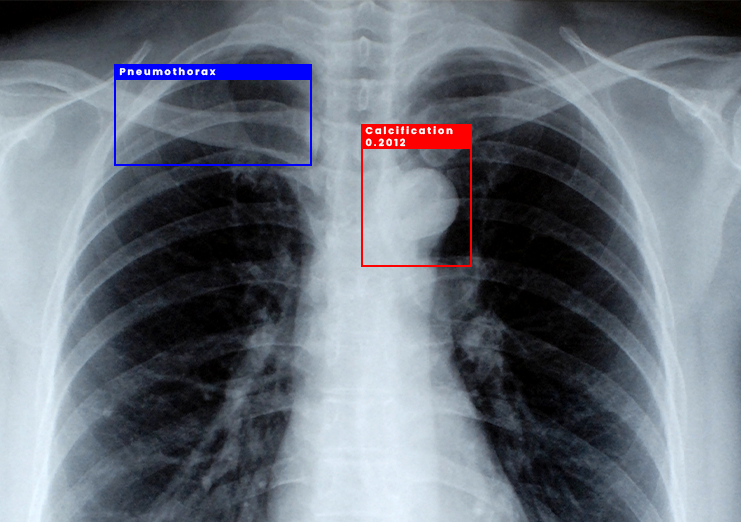

Bounding Box Annotation

Radiology & Diagnostics

AI models trained on annotated scans help radiologists detect diseases faster and with higher accuracy, reducing human error.